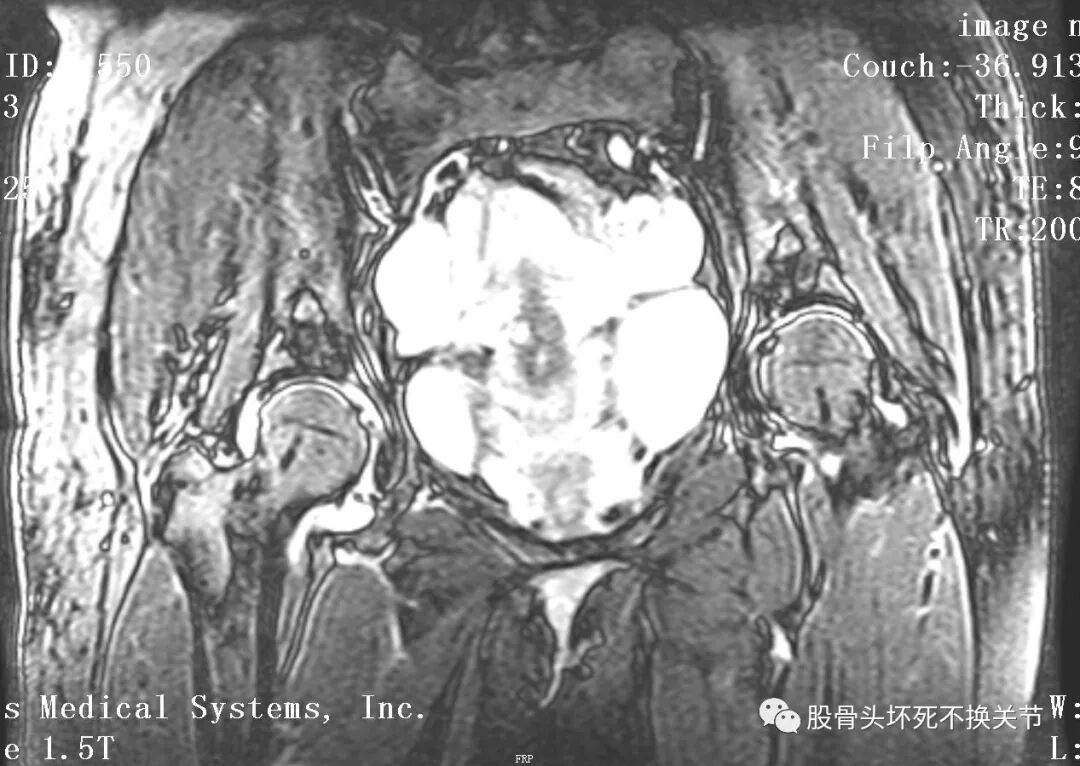

核磁共振是诊断疑难疾病的必备检查,更是诊断滑膜炎最直观、生动的手段。

点击放大观看双侧髋关节核磁共振片:

核磁共振检查显示右侧股骨头周围一圈亮度均匀的白色信号,就是平常所说的关节积液。